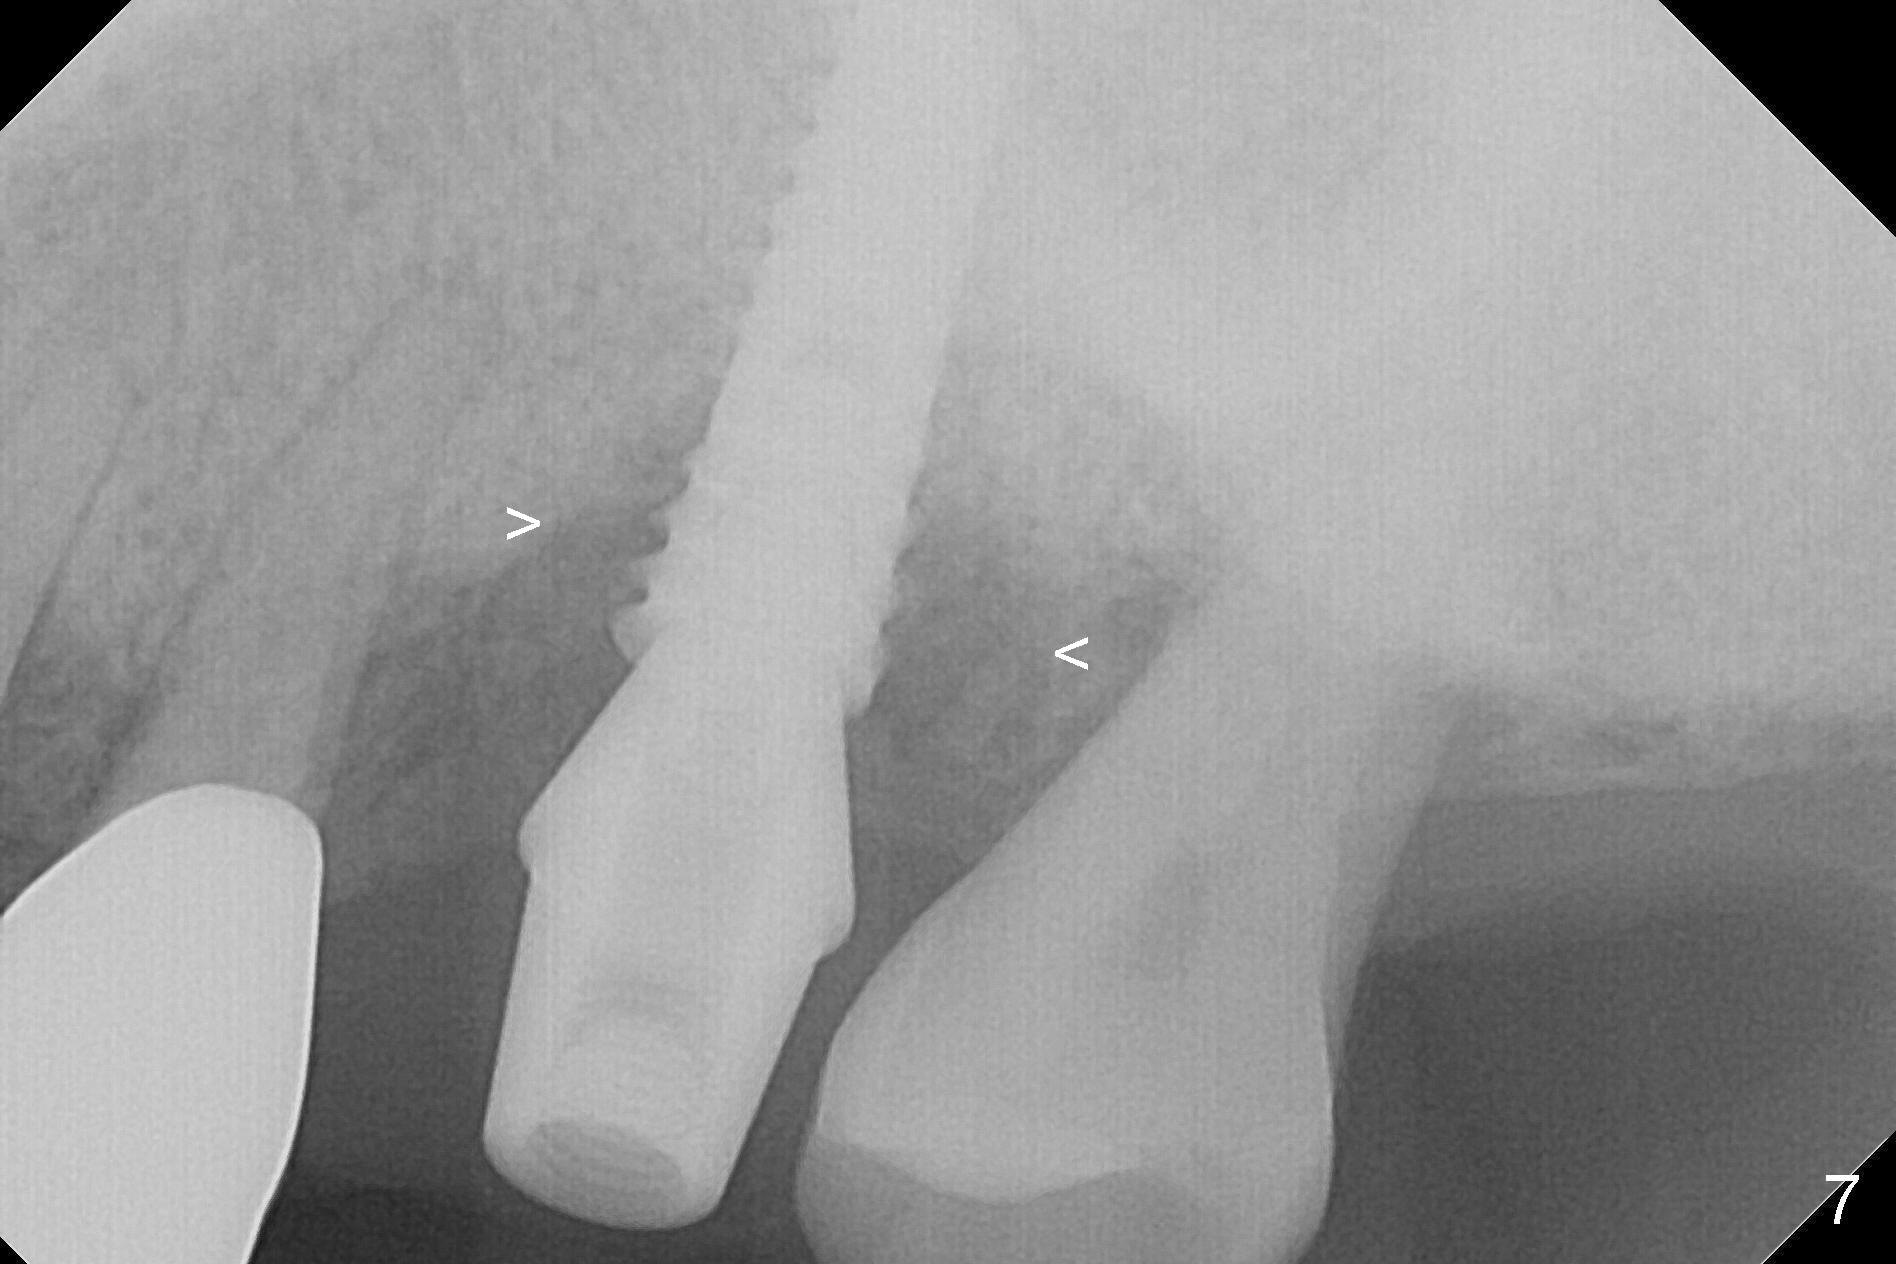

The amount of the bone graft mesial and distal the implant seems to reduce 3 and 4 months postop, respectively (Fig.6,7 arrowheads). When the acrylic is cut off 4 months postop, the bone graft is loose. The gingiva is unhealthy. The abutment and implant are loose. A healing abutment is placed (5x4 mm). The implant is torqued to 35 Ncm 6 months postop with the healing abutment reapplied. The patient will return for follow up nearly 9 months postop. A larger healing abutment will be used if the implant is stable. Two weeks later, use a smaller restorative abutment for easy impression. In fact the implant is unstable with #15 mesial shift due to abnormal occlusion with #17 (Fig.8). Bone density around the implant is low (* in Fig.9 (PA), 10,11 (CT sagittal, coronal sections)). A healing screw is placed for self healing. A 2nd option is to remove the implant (Fig.12), BEB (Fig.13) and place the implant deeper (Fig.14) or larger one (5.5-6.5x13 mm). The 3rd option is to place larger and longer implants (Fig.15 (tapered), 16 (cylindrical)). The implant access has partially closed 14 months postop, but there is a small buccal opening with sanguine exudate. Incision reveals severe bone loss around the implant; the mobile tooth #15 is extracted (Fig.17). After debridement and irrigation with normal saline, Vera Graft (Fig.18 *) and Collagen plug are placed with periodontal dressing.